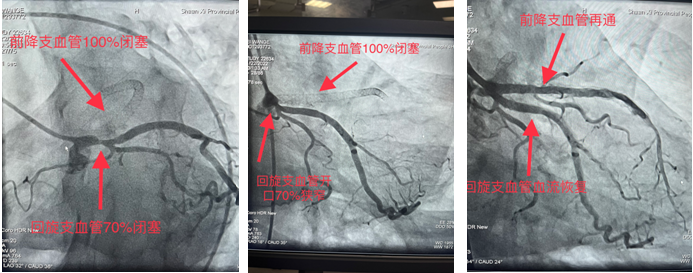

一患者月余前在外院行冠脉手术,手术未成功,遂前来三级片

求医,心血管内一科收入,并于11月22日安排冠脉手术为患者诊治病症。造影显示前降支支架内100%闭塞,回旋支开口70%狭窄。由于血管闭塞时间久,且之前支架内完全闭塞,术中出现心律缓慢、血压下降等危险因素。最终,在心血管内一科张勇主任医师、潘硕副主任医师、马彦鹏主治医师及介入放射诊疗手术室护师郭朝望、技师吴华楠等的默契配合和共同努力下,陈旧性冠状动脉闭塞血管得以再通,心脏血流恢复,生命体征随之好转,手术顺利完成。